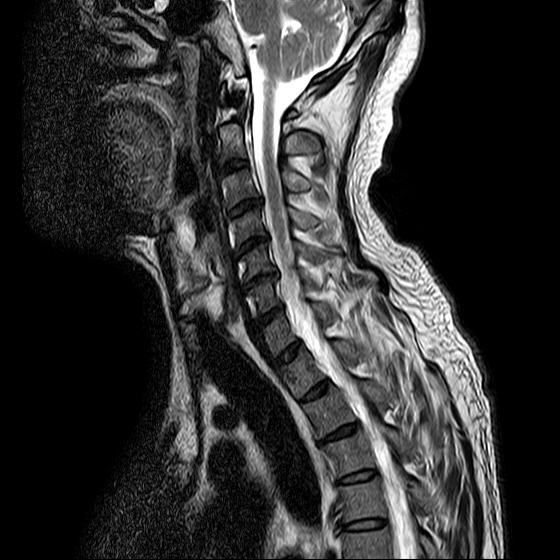

ũ Ͻ е鲲 ǰ ϴ. ڸ 4°Դϴ. ũ ϴ. (ڸǥغ ǥغ ) @ : 2014. 2.15 ĺ Ȳġ Ͽ. -> κ ǿ ġϿ պ ϱ. @ 2014. 3. 27 к mri, ct ũ ϰ ؾ Ѵٰ. @ ũ ġ ͳ Ͽ ڸǥغ Ͽ. ϱ : .(ó ) 2014. 4. 12() --- <1°> : Ͽ ȸ . 㳻 : (ڱ , Ӹ е ħ ˷. ¿ . ų ɰų Ҷ ̰ų ڼ . 201.4. 4. 13() ---<2°> 1. ħ Ͼ ¿ ȭ . 2. ħ е ħ . 3. ü ƮĪ ˷. ڼ ˷ֽŴ ϸ ڼ ùٸ ϸ Ÿ ˷ֽ Ư ƮĪ ϸ Ѱ پ 2014. 4. 14() ---<3°> : : پ(ó ߴ.) 㳻 : 1. ħ Ͼ ¿ ȭ . 2. ũ ˷ . 2014. 4. 14() ---<4°> : پ(ó .) 㳻 : 1. 繫ǿ ũ ٽ 2. ũ ˷ ϸ ڼ ϸ ȸ ̷ ɴ 2~3 ϸ ȸȴٰ Ͻô ū 븦 Ͽ ȸϵ ϰڽϴ. ȸ Ź帳ϴ. ũ mri Ȳ Դϴ. Ű 179 86 51 ()ijħ ڸǥغ ǥغ ˰Ե ͳ ˻ڷ õ ()ijħ ڸǥغ ǥغ ϱ ȣϽ 6C.ڸ 6C.ھ Ḳ 7C.Ȳġ 1T.Ȳġ 1T. κ ()ũ( ߰Ż) ڸ(߹) ũ(߰) Ը ũ(߰Ż)ġ, ()ijħ ڸǥغ ǥغ ϰ ߴ ġ 1. : 2014. 2.15 2. ġ : Ʒ(ô߿ ) , ȱ 3. **뺴 : ˾. Ƽ (ũ ) 4. ó : ڰ, 3 Ⱓ mypol()ó. ȭ. 3 5. ü ġ . |